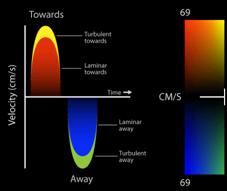

Por convención , el doppler espectral resultante muestra la velocidad en el eje de la Y y el tiempo en el eje X. El flujo que se dirige hacia el transductor, aparece por encima de la línea de base, mientras que el flujo que se aleja, se encuentra por debajo de la línea de base. El Doppler Color, (Figura 9) es una variedad de Pulsado que utiliza una escala de colores, representada, en el flujo laminar, con rojo (flujo que se acerca al transductor) y con azul el que se aleja. Cuando el flujo se hace turbulento, debido a una alteración funcional de la válvula, aparecen los colores amarillo y verde, reflejo de un aumento en la velocidad de la sangre al cruzar una válvula patológica anatómica o funcionalmente(13). (Figura 10)(Figura11)

Rojo positivo y laminar, se acerca a imagen transgástrica (140°), tracto salida transductor. Azul negativo, se aleja el transductor del ventrículo derecho (TSVD).

Figura 10 cuando la velocidad es elevada por flujo turbulento aparecen los colores amarillo y verde.

Figura 11: Izquierda: flujo turbulento por insuficiencia pulmonar leve. (TG profunda TSVD). Derecha: imagen a 66° medioesofágico 2 cámaras flujo turbulento por insuficiencia mitral moderada.